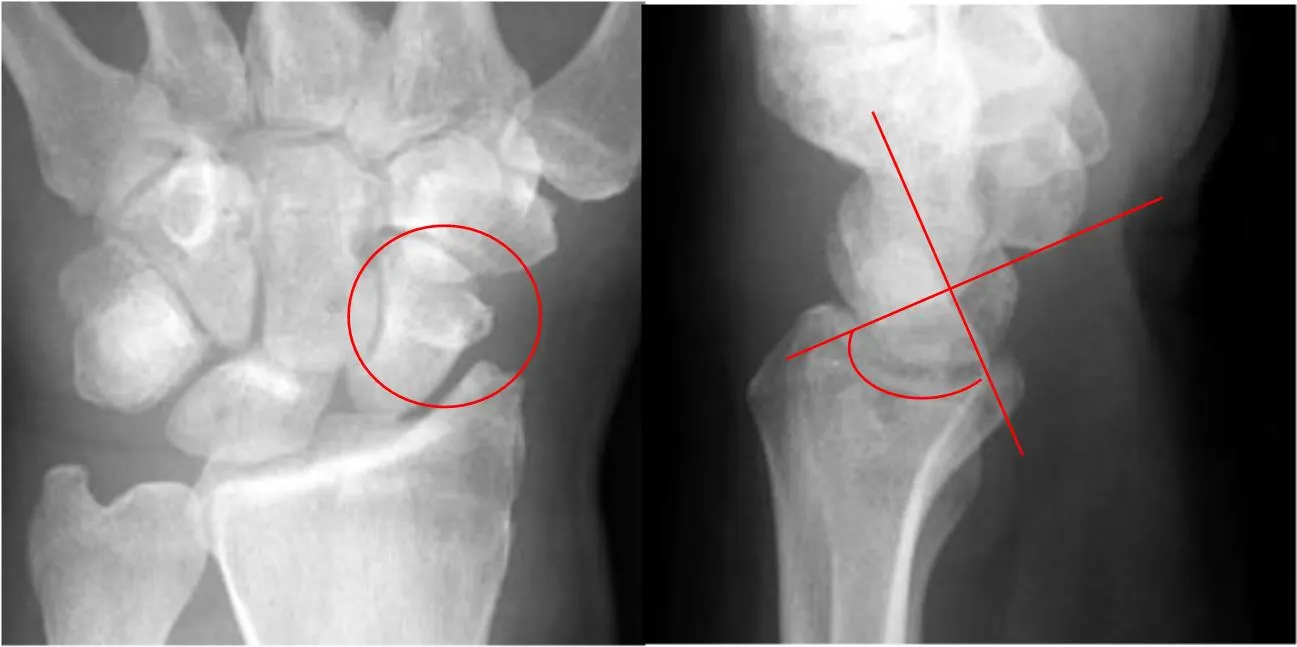

B. Stage I: Scapholunate dissociation

Wider than 4mm (Terry-Thomas sign)

Widening of the scapholunate joint : 3mm in PA view

Torn scapholunate ligament causes palmar tilting of scaphoid (rotary subluxation), creating scaphoid ring sign, Terry-thomas sign

C. Rotary subluxation of the scaphoid

D. Perilunate dislocation

Posterior dislocation of carpal bone while lunate maintains position with respect to the radius

Lunate bone remains in the lunate bone fossa

Other carpal bones dislocate in relation to the lunate